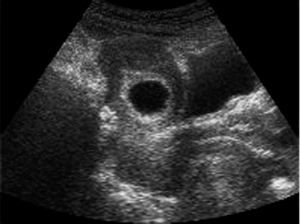

Spotting cysts

In many cases, ovarian fluid-filled cysts are harmless and won’t threaten your ability to conceive. However, your fertility might be affected if you have cysts due to endometrioses or PCOS. Laparoscopic surgery may be needed to remove the cysts, a minimally invasive and routine procedure.